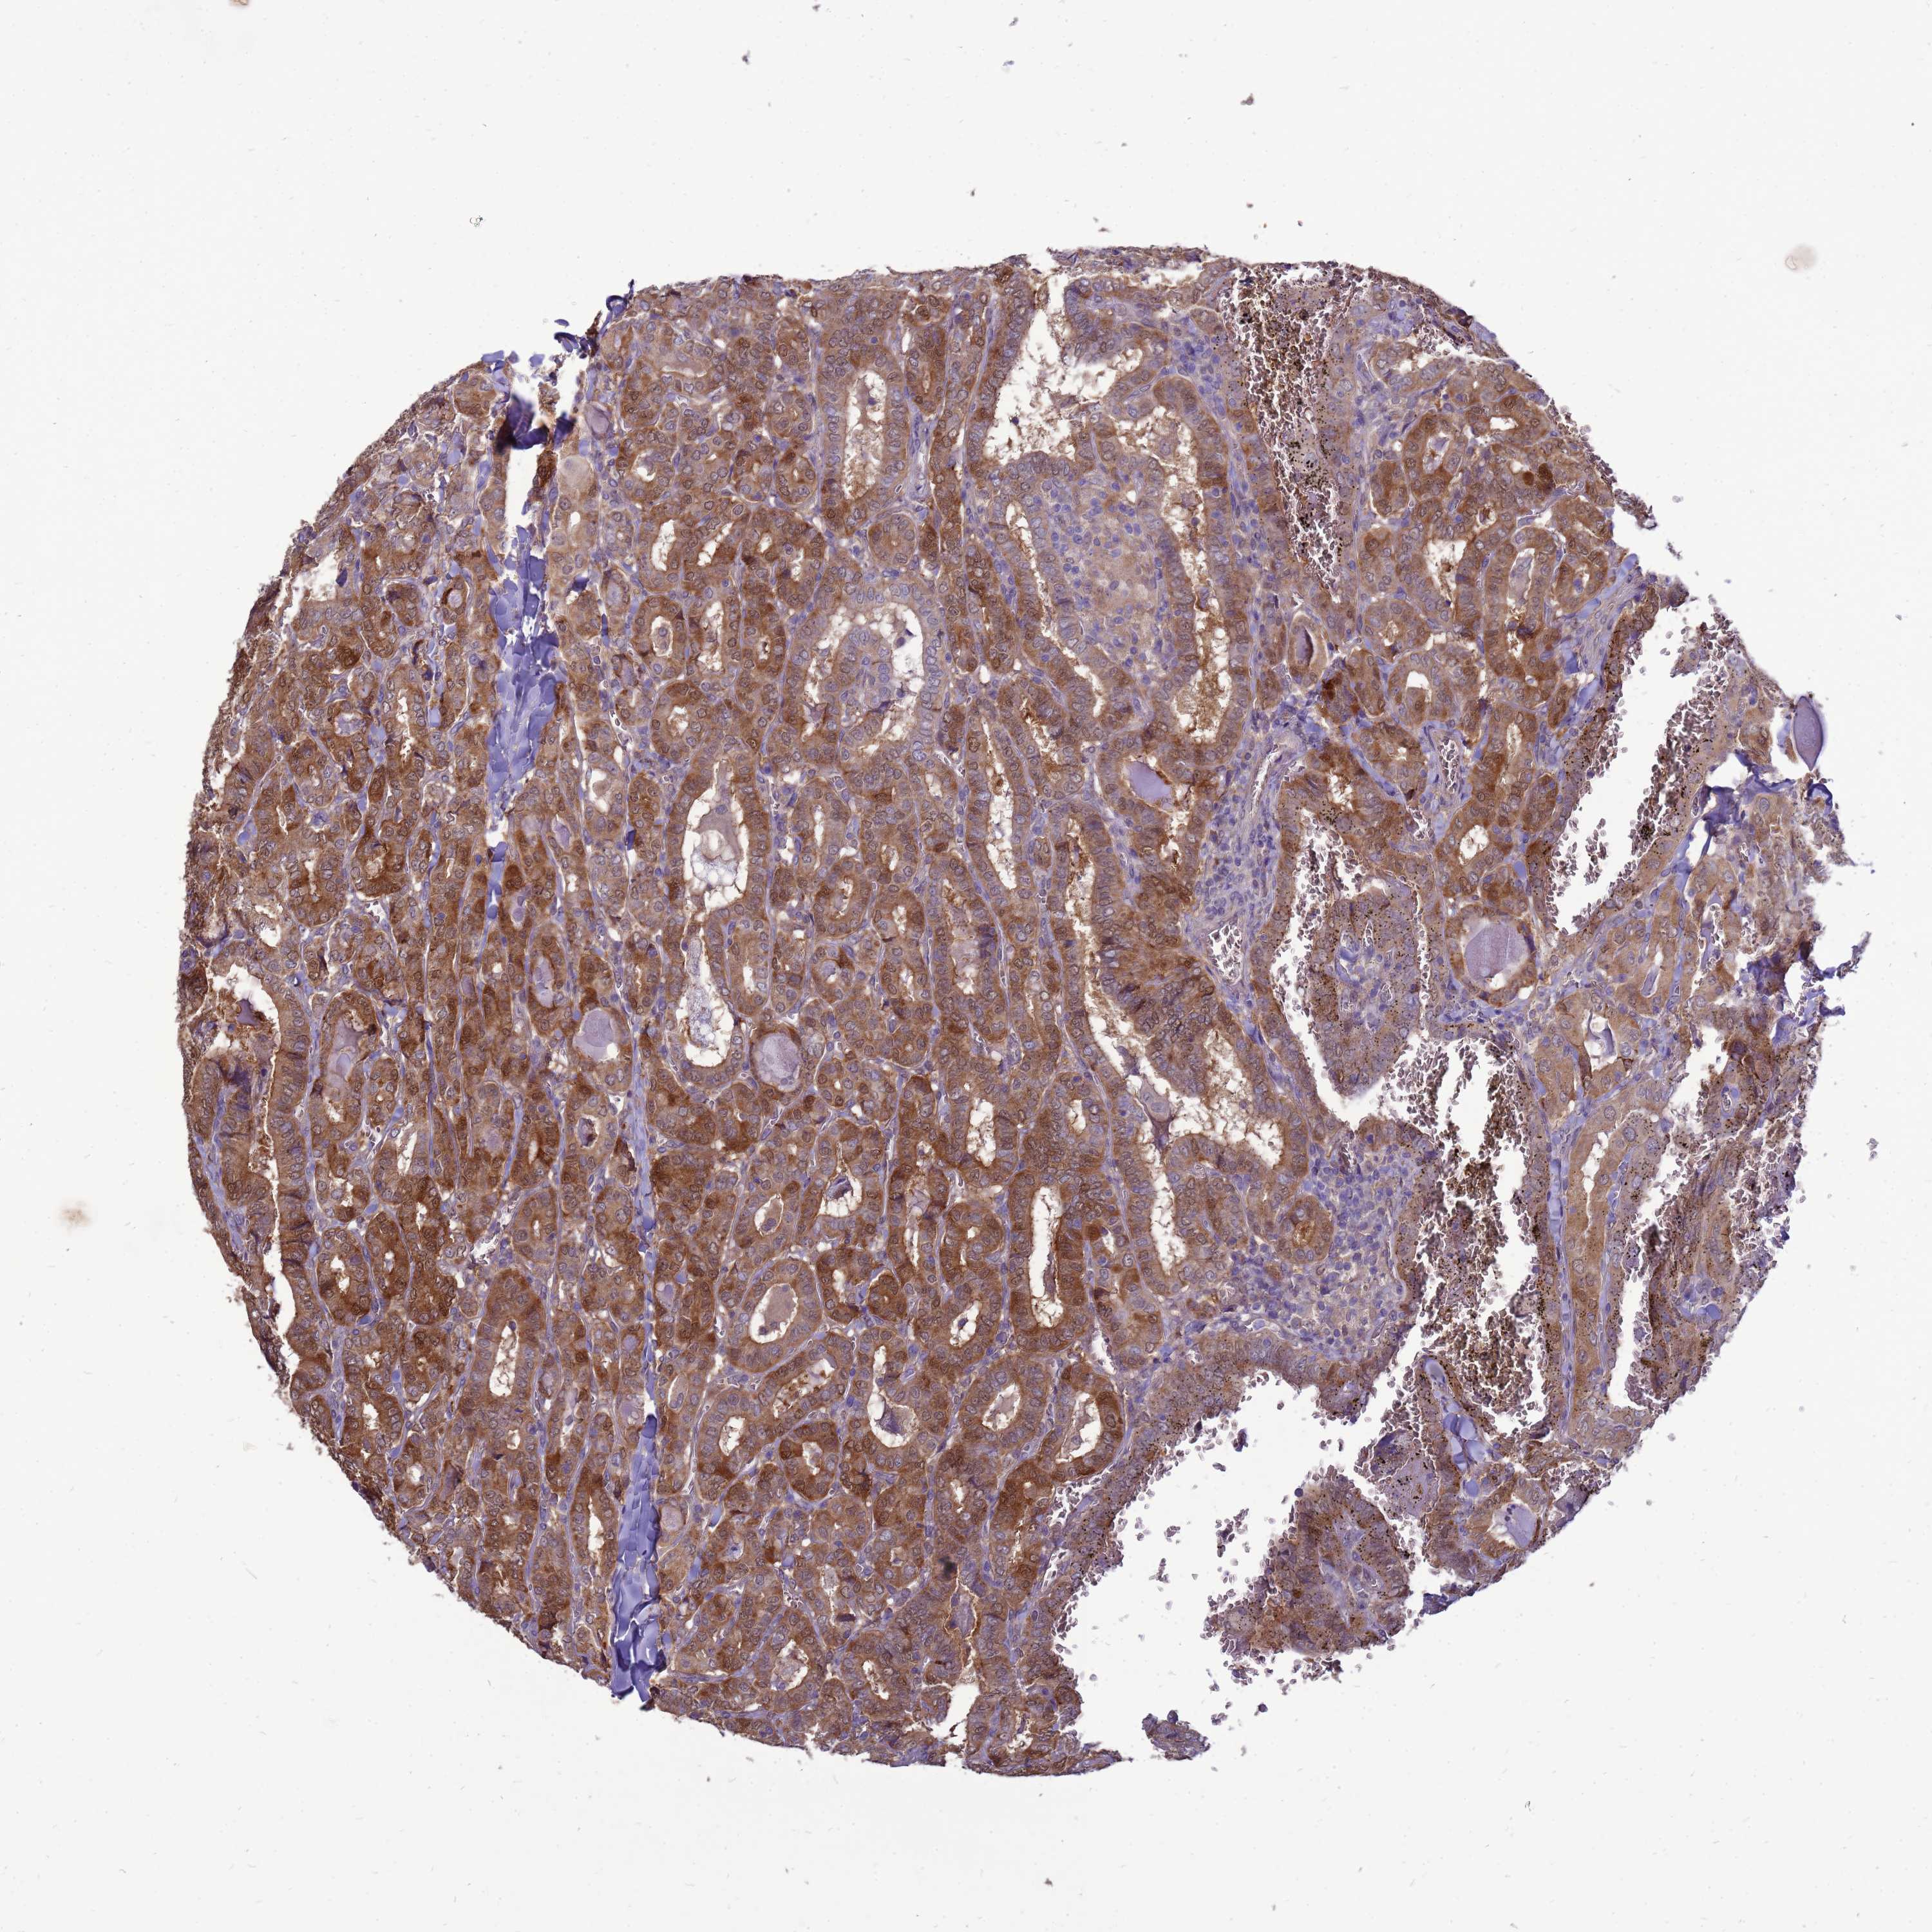

THYROID CANCER - Protein expressioni

A mouse-over function shows sample information and annotation data. Click on an image to view it in a full screen mode. Samples can be filtered based on level of antibody staining by selecting one or several of the following categories: high, medium, low and not detected. The assay and annotation is described here.

Note that samples used for immunohistochemistry by the Human Protein Atlas do not correspond to samples in the TCGA dataset.

Antibody stainingi

Antibody staining in the annotated cell types in the current human tissue is reported as not detected, low, medium, or high, based on conventional immunohistochemistry profiling in selected tissues. This score is based on the combination of the staining intensity and fraction of stained cells.

Each image is clickable and will lead to virtual microscopy that enables deeper exploration of all samples and also displays staining intensity scores, fraction scores and subcellular localization as well as patient and tissue information for each sample.

Antibody HPA045537

Staining

High

Medium

Low

Not detected

Intensity

Strong

Moderate

Weak

Negative

Quantity

>75%

75%-25%

<25%

None

Location

Nuclear

Cytoplasmic/membranous

Cytoplasmic/membranous,nuclear

Papillary adenocarcinoma, NOS

Follicular adenoma carcinoma, NOS